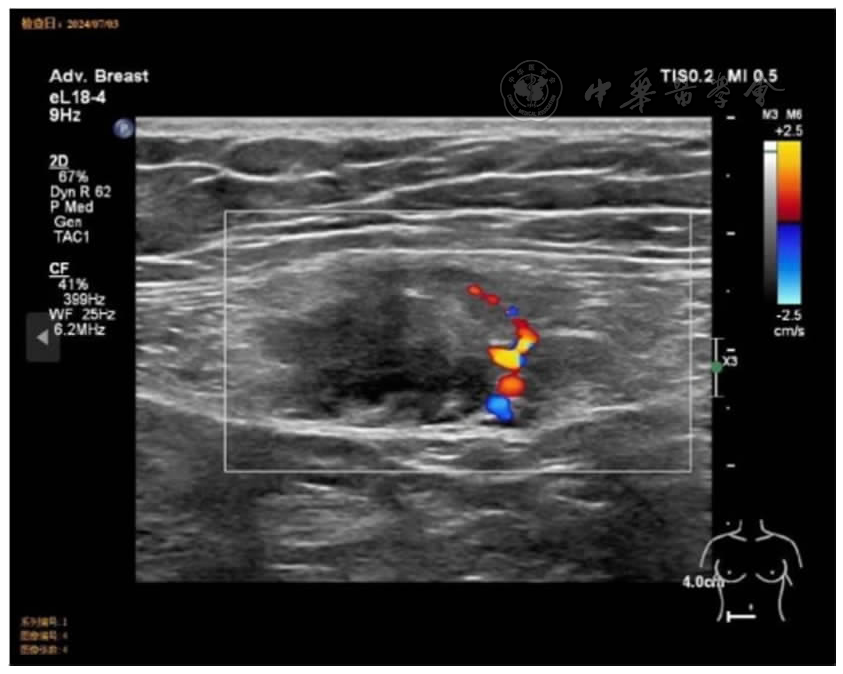

图1 腹壁病灶在超声下表现